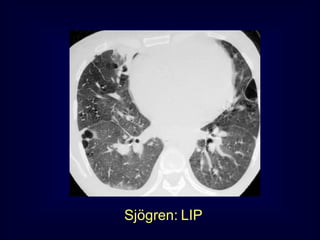

LIP = Lymphocytic Interstitial

Pneumonia

Benign lymphoproliferative

disorder

Diffuse interstitial infiltration of

mononuclear cells

Not limited to the air ways as

in follicular Bronchiolitis

Sjögren: LIP

Rarely idiopathic

In association with:

Sjögren’s syndrome

Immune deficiency syndromes, AIDS

Primary biliary cirrhosis

Multicentric Castlemean’s disease

Sjoegren disease

Dry eye and dry mouth

Fibrosis, bronchitis and bronchiolitis

LIP

Up to 40 x increased risk for lymphoma (mediastinal

adenopathy) and

2 x times increased risk for neoplasma